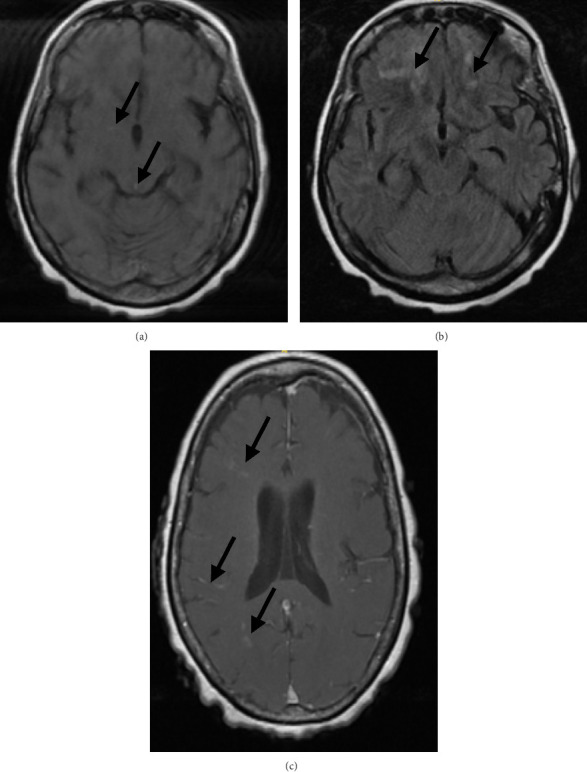

一名65岁妇女,表现为肺炎球菌败血症和脑膜炎。尽管适当的抗菌药物治疗和静脉注射地塞米松,她的精神状态没有改善。脑显像提示脑血管炎。开始大剂量静脉注射甲基强的松龙治疗后,病情迅速好转。完成3周口服泼尼松逐渐减少治疗一周后,患者的神经认知缺陷复发。更广泛的诊断评估,包括常规血管造影,再次与脑血管炎的推定诊断一致。大剂量静脉注射甲基强的松龙和较长时间的口服强的松逐渐减少导致她的疾病缓解,精神状态和左侧偏瘫有明显改善。脑血管炎是肺炎球菌性脑膜炎的一种罕见但潜在致命的并发症,可能难以识别和治疗。脑活检在诊断中的作用尚不清楚,由于其罕见性,该病的治疗缺乏确凿的循证数据。

A 65-year-old woman presented with pneumococcal sepsis and meningitis. Despite appropriate antimicrobial therapy and intravenous (IV) dexamethasone, her mental status did not improve. Findings of brain imaging were suggestive of cerebral vasculitis. Her condition improved rapidly with the initiation of high-dose IV methylprednisolone therapy. One week after completion of a 3-week oral prednisone taper, the patient's neurocognitive deficits recurred. A more extensive diagnostic evaluation, including conventional angiography, was again consistent with a presumptive diagnosis of cerebral vasculitis. High-dose IV methylprednisolone and a more prolonged taper of oral prednisone led to remission of her disease, with marked improvement in mental status and left-sided hemiparesis. Cerebral vasculitis is a rare but potentially lethal complication of pneumococcal meningitis that may be difficult to recognize and treat. The role of brain biopsy in diagnosis is unclear, and due to its rarity, management of this condition lacks conclusive evidence-based data.